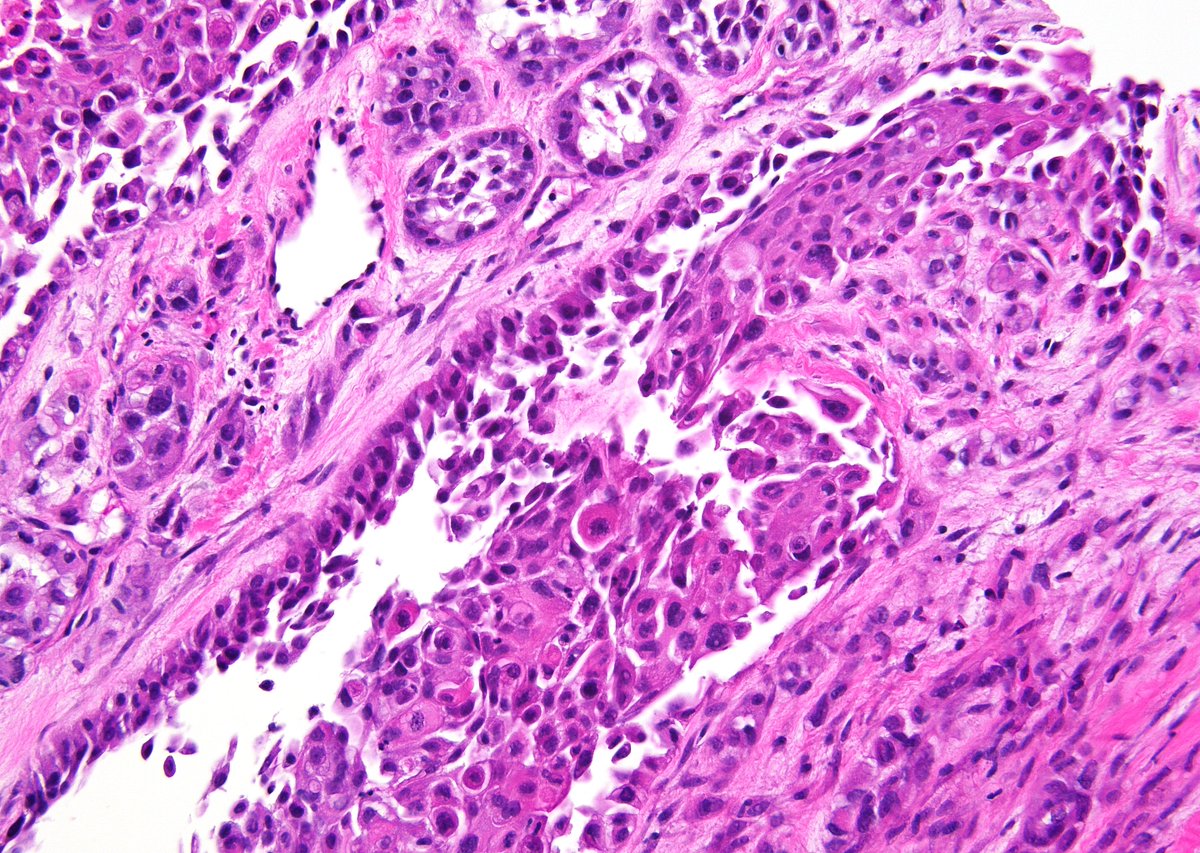

Tumor with an EGFR p.G719A mutation. What type of tumor is shown? Answer: kikoxp.com/posts/18719 #PathTwitter #MolPath #MedTwitter #PathArt